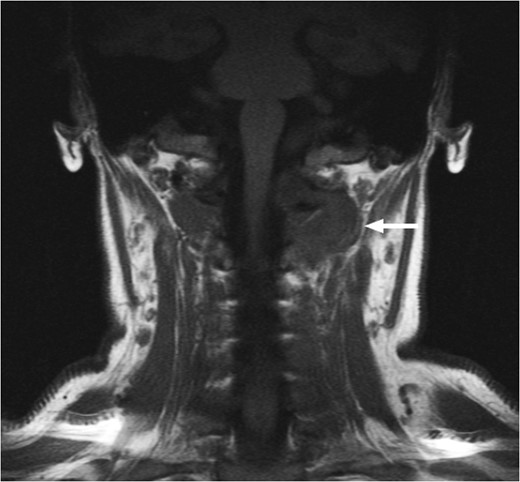

T1-weighted MRI showing the lesion eroding through the left basioccipital skull, impinging the dura overlying the left cerebellum.